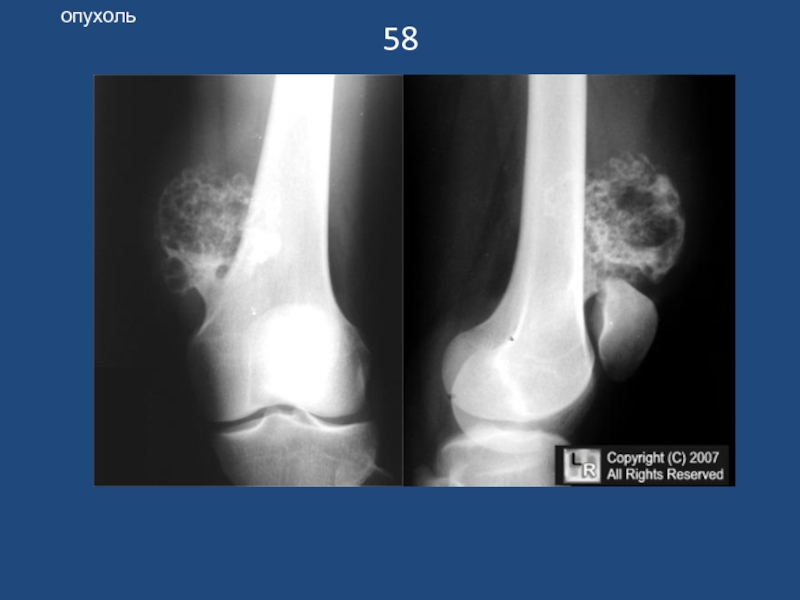

Слайд 5958

опухоль